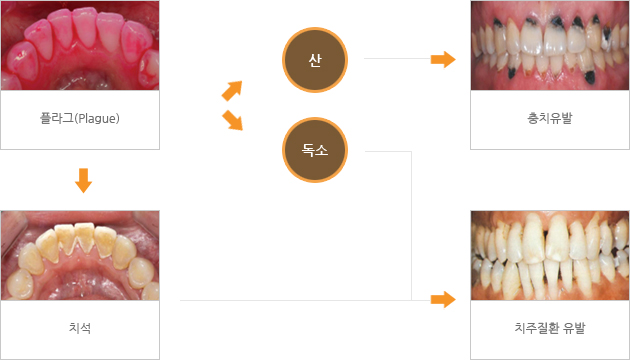

아무리 정성스럽게 양치질을 해도 충치가 생기기 쉬운 분들이나 잇몸이 약한 분들이 있는데 이런 분들은 스케일링을 언제 받았는지 생각해 볼 필요가 있습니다. 치아 사이에 남아 있는 음식은 치태와 치태의 주요 원인이 되며 잇몸과 치아에 다양한 구강질환을 일으키게 됩니다. 문제는 치석은 양치질로 제거되지만 치석이 굳어서 생긴 치석은 양치질이나 치실로도 제거할 수 없다는 점인데, 따라서 정기적인 스케일링으로 치석을 제거해야 합니다.그런데 스케일링의 이 냉증이나 그 이후에 나타나는 출혈이 부작용이라고 생각해서 치료를 제때 받지 않는 분들이 많습니다. 스케일링 이 시린 것은 정말 부작용인지 런던 오후 치과에서 알아보겠습니다. 스케일링이란?

우선 스케일링이 뭘까요? 딱딱한 물질을 긁거나 비늘을 제거한다는 의미의 스케일링은 치아 표면과 치아와 잇몸 사이에 남아 있는 치석과 치석을 제거하는 시술 방법입니다. 이물질을 물리적으로 제거하고 치아 표면을 매끄럽게 하는 등 예방 목적이 가능한 치료 방법 중 하나이며 착색 예방에도 도움이 되므로 치아 미백에도 도움이 됩니다. 스케일링이 시린 이유는?

치석은 치아 표면에만 가능하기 때문에 잇몸과 치아 사이에도 생길 수 있습니다. 이때 스케일링을 통해 치석이 제거되면 치아 뿌리가 외부로 노출되지만 코트를 입고 벗을 때 나타나는 외로움처럼 일시적으로 이가 시리게 느껴질 수 있습니다. 이런 증상들은 잇몸이 다시 올라가기 전까지 나타난다고 볼 수 있고 치태의 양이 많거나 스케일링을 정기적으로 받지 않은 분들이라면 증상이 더 심해질 수 있습니다.대부분의 경우 시간이 지나면 사라지게 되는데 잇몸에 염증이 있는 분이라면 더 오랜 시간 증상이 나타날 수 있고, 3주 정도 지나도 지속된다면 치과의원에 내원하여 잇몸 상태를 확인해야 합니다. 출혈은 왜 발생하나요?